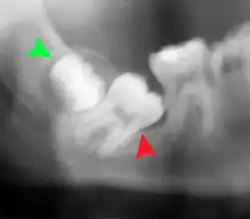

Impacted wisdom teeth are often described by the direction of their impaction (forward tilting, or mesioangular being the most common), the depth of impaction and the age of the patient as well as other factors such as pre-existing infection or the presence of pathology (cysts, tumors or other disease).[5]: 143–144 Each of these factors is used to predict the difficulty (and rate of complications) when removing an impacted tooth, with age being the most reliable predictor[8] rather than the orientation of the impaction.[9]

Coronectomy

Coronectomy is a procedure where the crown of the impacted wisdom tooth is removed, but the roots are intentionally left in place. It is indicated when there is no disease of the dental pulp or infection around the crown of the tooth, and there is a high risk of inferior alveolar nerve injury.[32]

Coronectomy, while lessening the immediate risk to the inferior alveolar nerve function has its own complication rates and can result in repeated surgeries. Between 2.3% and 38.3% of roots loosen during the procedure and need to be removed and up to 4.9% of cases require reoperation due to persistent pain, root exposure or persistent infection. The roots have also been reported to migrate in 13.2% to 85.9% of cases.[32]